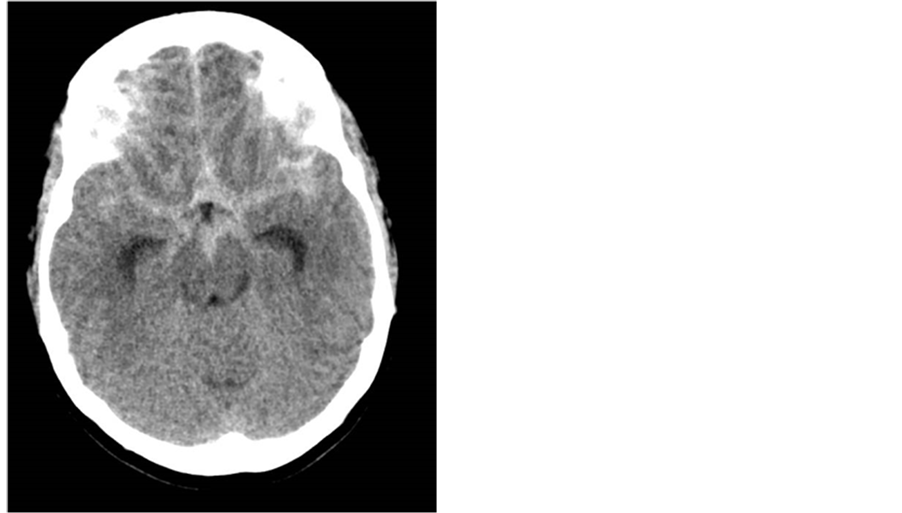

A head CT revealed a subarachnoid hemorrhage, and a formal cerebral angiogram showed an ACOM (anterior communicating artery) aneurysm not amenable to coiling [Figure 2].

Figure 2. Admission head CT showing diffuse SAH with hydrocephalus.

An External Ventricular Drain (EVD) was placed, and the patient was taken for an aneurysmal clipping. She had a baseline cardiac 2DECHO done that showed a normal EF 55% - 60%. The first 3 days after her surgery were uneventful, but on day four, in spite of nimodipine use, blood transfusion to stabilize hematocrit, and albumin to improve oncotic pressure, a Transcranial Doppler (TCD) showed increased velocities. On day five she developed an altered mental status, and on day six her urine output increased. The patient was initially placed on neosynephrine, with norepinephrine added to maintain cerebral perfusion. Her repeated 2DECHO showed decreased left ventricular systolic function with an EF drop to 40% - 50% and anteroseptal wall akinesis.

Due to a further increase in velocities on her TCD, a formal cerebral angiogram was performed next day, which showed moderate vasospasm, which was then treated with intra-arterial verapamil. The same day, the patient became drowsy. The cerebral angiogram was subsequently repeated, and again resulted in intra-arterial administration of verapamil. Due to the use of multiple pressors, the patient’s cardiac condition worsened and she developed Takotsubo syndrome. In an effort to reduce the use of pressors, neosynephrine was weaned off and I.V. milrinone was started. This resulted in a significant drop in blood pressure, EKG changes, a troponin leak, and significant tachycardia, which resulted in the discontinuation of milirinone use. The patient continued to receive verapamil intra-arterially, which led to the resolution of vasospasms. The patient’s medical and neurological condition improved, and she was eventually discharged to an acute rehab facility.